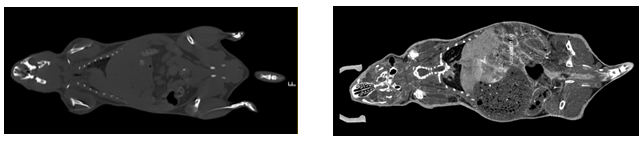

CBCT的一局限性是密度分辨率不够,对部分软组织解剖结构特别是软组织病变显像不如螺旋CT清晰。所以,在Micro CT的小动物实验上,一般会使用造影剂来增加内脏的对比度。